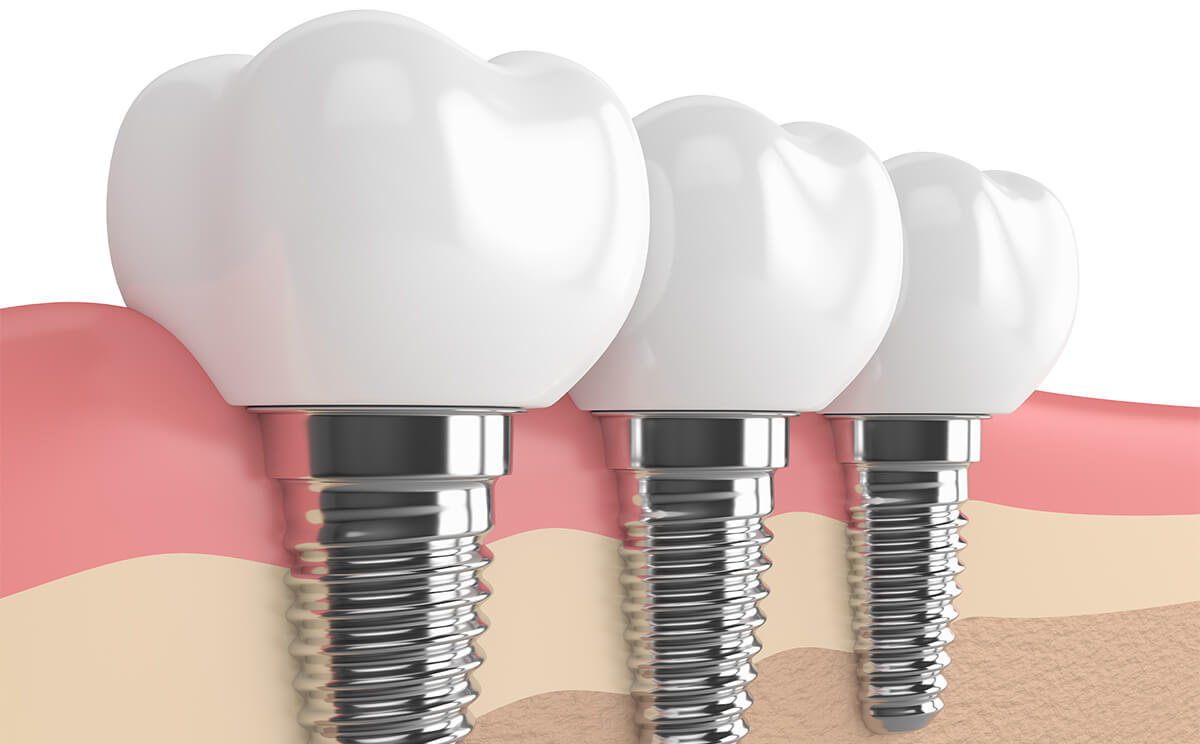

Same-day teeth implants work best when restoring an entire arch or all of your teeth using all-on-four or all-on-six implants. In traditional implant treatment, patients wait months for their implant to integrate into their bone system before receiving a supportive abutment or restoration to replace lost teeth. With teeth in a day, there’s no waiting period between implant placement and getting new teeth.

On the date of your surgery, your dental surgeon will place four or six implants strategically in your mouth to support your new teeth. These implants are placed at an angle within your jaw where your bone is thickest. Once the implants are in place, we’ll attach an arch of fully functional temporary teeth for you until the customized permanent teeth can be made. Your smile is restored in one day rather than waiting months to receive new teeth.